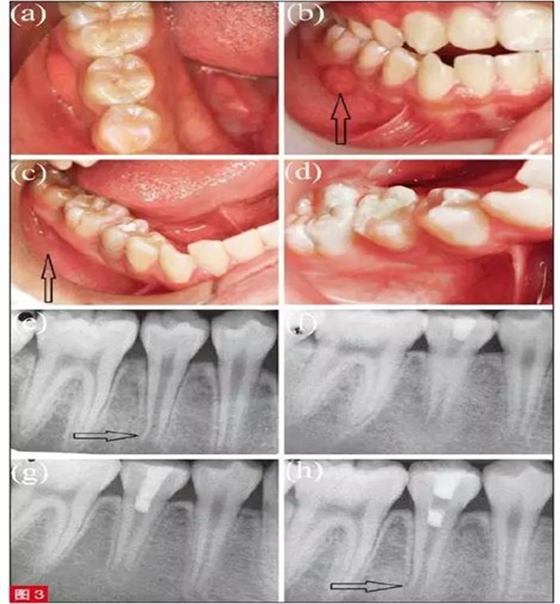

患者為9 歲男童,主訴右側(cè)牙齒咀嚼痛2 周。6 個(gè)月前患者右下頜疼痛腫脹,當(dāng)時(shí)未接受任何治療。臨床檢查,見(jiàn)45 牙畸形中央尖折斷,未見(jiàn)齲壞(圖3a),45 和46 間牙齦見(jiàn)竇道(圖3b)。45 叩診(+), II 度松動(dòng),冷測(cè)及EPT 測(cè)試均無(wú)反應(yīng)。根尖片示,牙根未發(fā)育完全,根尖孔敞開(kāi)且根尖周見(jiàn)透射影(圖3e)。依照臨床和影像檢查,45 初步診斷為慢性根尖膿腫。由于牙根尚未發(fā)育完全、根尖孔敞開(kāi),推薦使用MTA 為其進(jìn)行牙髓再生治療?;颊咧橥夂?,即刻治療。

具體治療過(guò)程如下:以2% 利多卡因(3MDeutschland GmbH,德國(guó))局部浸潤(rùn)麻醉45 牙,橡皮障隔離。高速渦輪手機(jī)在噴水冷卻下進(jìn)行開(kāi)髓。此時(shí),根管冠方可見(jiàn)呈粉色、質(zhì)地連續(xù)的活髓組織。最終診斷為45 部分牙髓壞死伴慢性根尖膿腫。隨后切除冠部壞死牙髓組織,根管內(nèi)20ml 3%NaOCl 溶液沖洗3 分鐘,再使用10ml 生理鹽水沖洗3 分鐘。無(wú)菌紙尖干燥根管后,導(dǎo)入氫氧化鈣糊劑(圖3f),使用IRM 暫封材料(Dentsply Caulk, 美國(guó))進(jìn)行冠方封閉。患者2 周后復(fù)診,述治療后未出現(xiàn)疼痛,臨床檢查,見(jiàn)頰側(cè)竇道完全消失(圖3c)。45 牙叩診(+-),且變?yōu)镮 度松動(dòng)。在橡皮障隔離下,去除IRM 暫封材料,20ml 3%NaOCl 溶液沖洗3 分鐘,再使用10ml 生理鹽水沖洗3 分鐘,以完全清除氫氧化鈣糊劑。無(wú)菌紙尖干燥根管后,在活髓組織上放置MTA( ProRoot,Dentsply Tulsa Dental, 美國(guó)), 開(kāi)髓孔由Cavit (GCCorp,日本)和玻璃離子水門汀分層封閉(圖3g)。8 個(gè)月后復(fù)查,45 牙無(wú)任何癥狀,叩診、捫診均無(wú)不適,冷測(cè)和EPT 測(cè)試顯示牙髓有活力,臨床檢查均表現(xiàn)正常。根尖片示牙根持續(xù)發(fā)育,根尖孔逐漸閉合,根尖周透射影完全消失,根管壁明顯增厚,且根尖孔縮窄(圖3h)。去除Cavit 暫封材料,使用復(fù)合樹(shù)脂永久充填(Filtek Z350 XT; 3M ESPE Dental Products,美國(guó))(圖3d)。